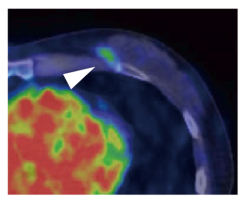

臨床試験では、既にHER2陽性であることが確認され、トラスツズマブで治療中の乳がん患者の協力を得ました。文書による臨床試験への参加同意が得られた患者14症例に対して、通常治療用量の100分の1以下※9に相当する64Cu-DOTA-Trastuzumabを静脈注射し、6、24、48時間後にPET検査を行いました。その結果、最小直径2.0cmまでの腫瘍を描出できることが分かり、ほとんどの症例でHER2陽性乳がんの原発巣に一致したシグナルを観察しました(図2)。転移巣の診断では、特に脳転移の描出に優れることが分かりました(図3左)。針生検でHER2陽性乳がんの肺転移が確定した症例では、転移巣の位置にシグナルを認め、針生検と画像診断の結果が一致することを確認しました(図3右)。また胸骨/縦隔リンパ節転移症例では、治療に伴いがん組織が縮小する様子を追跡できました(図4)。さらに、腎細胞がんとHER2陽性乳がんの両方のがんを有する症例(重複がん)では、HER2陽性脳転移巣が描出される一方、腎細胞がんではシグナルを認めず、今回のPET検査がHER2陽性腫瘍を特異的に検出することが分かりました。

図2 HER2陽性乳がん原発巣におけるトラスツズマブPETプローブの集積

トラスツズマブを用いる術前化学療法中のHER2陽性乳がん患者に64Cu-DOTA-Trastuzumabを静脈注射しPET検査したところ、左乳房の原発巣の位置に一致したシグナルを観察した(矢頭)。左下の赤い部分は血中のシグナル(心臓内腔)を示す。